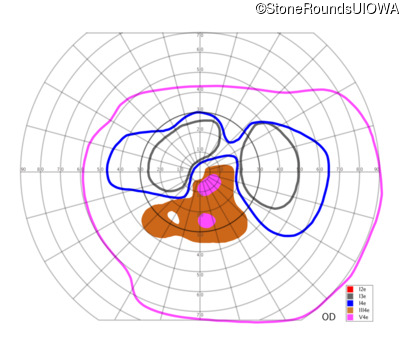

AR Stargardt Disease (IIA)

AR Stargardt Disease (IIA)

| Age at visit: 12 years |

| Age at visit: 13 years |

| Age at visit: 15 years |